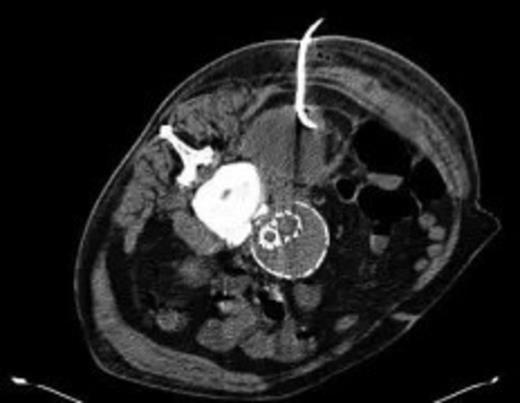

The patient's condition improved quite rapidly and the intravenous antibiotics were stopped and replaced with oral ciprofloxacin upon microbiological advice (for a total of six weeks). The drain was removed after 2 weeks when the series of repeat CT scans showed the abscess had nearly completely resolved (Fig. 5). Further CTs on follow up at 6 weeks and 3 months post discharge show no collection at all. At the last clinic visit 6 months following his last admission the patient was enjoying good health.

Near complete resolution of psoas collection after 2 weeks of intravenous antibiotics